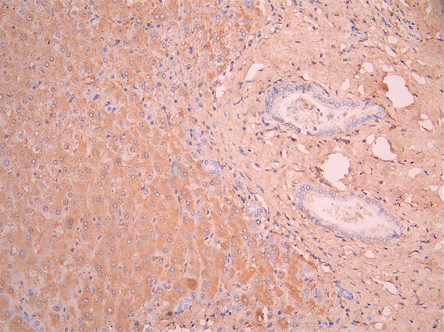

IHC image of CSB-RA001939MA1HU diluted at 1:50 and staining in paraffin-embedded human liver tissue performed on a Leica BondTM system. After dewaxing and hydration, antigen retrieval was mediated by high pressure in a citrate buffer (pH 6.0). Section was blocked with 10% normal goat serum 30min at RT. Then primary antibody (1% BSA) was incubated at 4°C overnight. The primary is detected by a Anti-Human lgG, Fcy Fragment Specific labeled by HRP and visualized using 0.05% DAB.

IHC image of CSB-RA001939MA1HU diluted at 1:50 and staining in paraffin-embedded human liver cancer performed on a Leica BondTM system. After dewaxing and hydration, antigen retrieval was mediated by high pressure in a citrate buffer (pH 6.0). Section was blocked with 10% normal goat serum 30min at RT. Then primary antibody (1% BSA) was incubated at 4°C overnight. The primary is detected by a Anti-Human lgG, Fcy Fragment Specific labeled by HRP and visualized using 0.05% DAB.